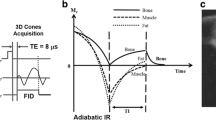

The UTE sequence was based on a slab selective excitation and radial stack of stars readout starting in the center of k-space. A partial Fourier factor of 0.8 was used in phase encoding direction to reduce acquisition time. The 3D T1 GRE sequence was based on slab selective excitation in combination with Cartesian sampling and partial Fourier encoding in read out direction to keep the echo time short. Finally the 3D FRACTURE sequence [10] was based on a Cartesian multi-echo 3D T1 GRE sequence with four echoes acquired. During postprocessing, a magnitude summation of all echoes was performed and afterwards the last echo was subtracted to create a CT-like bone contrast. Both the 3D T1 GRE and the 3D FRACTURE sequences were accelerated using Compressed SENSE. Detailed scan parameters of the CT-like MR-based sequences are displayed in Table 2. To achieve CT-like bone contrast of the three CT-like MRI sequences, all image intensities were inverted after image reconstruction.